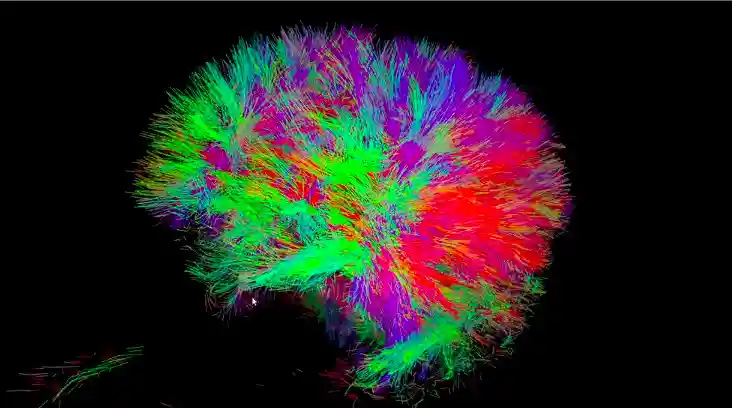

In the latest years, I have developed/collected some tools for brain tractography, from inclusion in html, to 3Dprinter conversion to other manipulations. Codes is mostly in matlab and we should move in Python, moreover the converter from Trackvis to STL for 3Dprinting or Augmented Reality is not good. I am open minded to other ideas for tractography.

Wacky brain explosions Vol II.

Are you asking to yourself 'how can the year 2020 get more interesting?. The answer is simple: by using a particle simulator to explode some brains at the comfort of your home, in a completely safe virtual environment.

After concluding my previous hackaton project with 'more research is needed', here I am planning to continue exploding more brains in many of ways. All in the name of neuro-science, of course!

I wrote TRAMPOLINO during BrainHack School with the idea of building a tool to easily do tractography across different packages. My vision now is to make it become the Swiss Army Knife for tractography: a tool able to try out things, even when you do not have the right software installed (!!!). The dream would be typing just 'trampolino --corpus-callosum' and getting the tractogram for a corpus callosum to play with!

Matching white matter fiber tracts across subjects

With diffusion MRI, we can track the axon fibers in the brain white matter. Although a certain level of variability exists, we still believe that there are a substantial amount of fiber bundles/tracts that are common across subjects. Thus, matching the fiber bundles across subjects could help us understand the common architecture of white matter in the human brain.